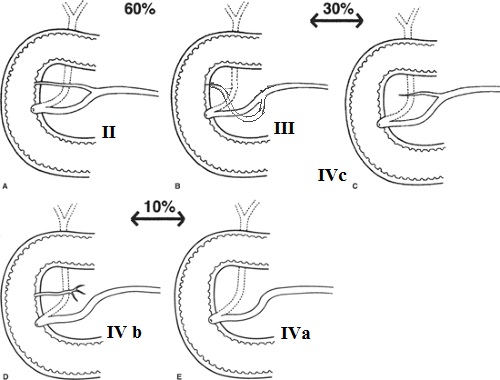

ou petit caroncule ) . La situation du canal Wirsung et

canal Santorini est un peu varie en troi type

| |

| Type I : C'est la disposition

canalaire embryonaire |

| Type II : presente une

disposition classique ( 60%) |

| Type III : Il y avait une anse du

canal Wirsung a la papille mineur |

| Type IV a,b,c : En presence un

canal accessoire oblitere au niveau de la

papille mineur , ou en jonction avec le

canal principale |